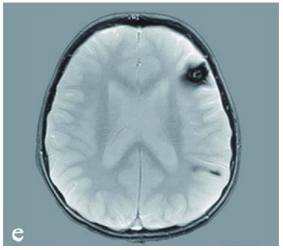

复查核磁显示,不仅原先的脑干海绵状血管瘤已生长到4×3.5×3cm,还在左额叶及顶叶也发现一个致痫病灶,同样是海绵状血管瘤。

来自母亲的遗传

很明显,楠楠所患的是多发性海绵状血管瘤,这让医生不由得开始怀疑,这个3岁小女孩身上可能存在家族遗传基因。果然,在对楠楠母亲进行基因检测后,医生发现楠楠和母亲体内都藏着一个名为CCM1基因的新发突变。而在楠楠母亲的核磁上,也发现了多个海绵状血管畸形的小病灶,但楠楠母亲至今并未出现任何症状。